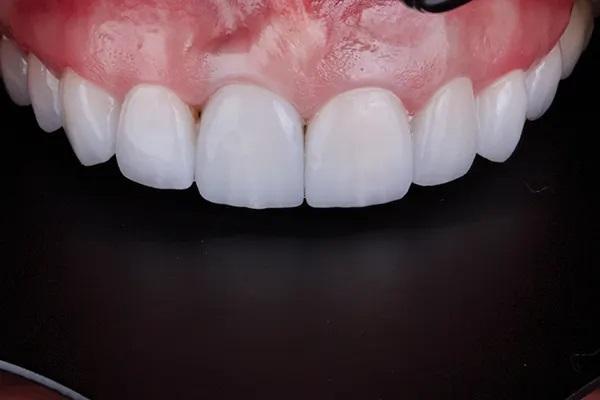

В данном случае был выбран GC Initial Press MT (GC America) (MT расшифровывается как "средняя прозрачность"). При таком уровне прозрачности специалист может, с одной стороны, замаскировать некоторые различия в оттенках, но, с другой стороны, впитать часть основного цвета, чтобы добиться очень живого и естественного результата. Все коронки были спроектированы с вырезом на лицевой стороне. Керамика была нанесена слоями, чтобы имитировать естественный трехмерный вид внешний вид натурального зуба и получить соответствие с внешним видом оставшихся в полости рта интактных зубов. Глазирование и полировка проводилось алмазной полировочной пастой, завершая лабораторные этапы (Фото 12 и Фото 13).

Фото 12. Примерка окончательных реставраций на модели.

Фото 13. Окончательная реставрация после полировки и глазирования.